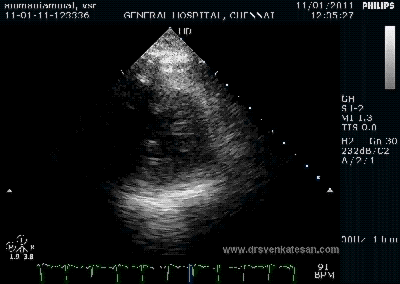

Here is 55 year old women came with extensive anterior MI with lower septal rupture.(She belonged to type 3 of the above scheme)

)

Note the septal rupture is visible even in 2D Echo

Color flow showing significant shunting from LV to RV.This shunt depends upon the LV contractile function, LVEDP and ofcourse the RV pressure

If there is severe RV dysfunction or bi ventricular dysfunction flow across the defect is inconspicuous.Brisk left to right shunting may be an indirect marker for good LV systolic function and absence of significant pulmonary hypertension.Both imply a better outcome.

The main determinant  of survival is the  underlying LV dysfunction and associated co morbidity(Renal function ) and complications .